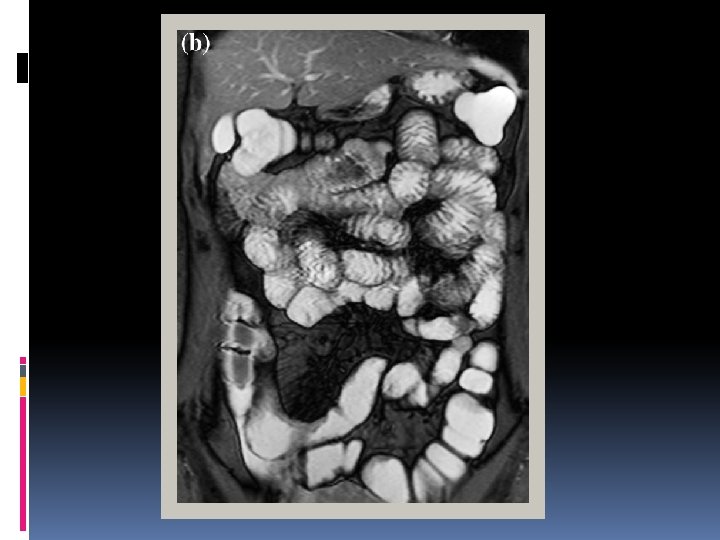

Inflammatory bowel disease • Bowel wall thickening